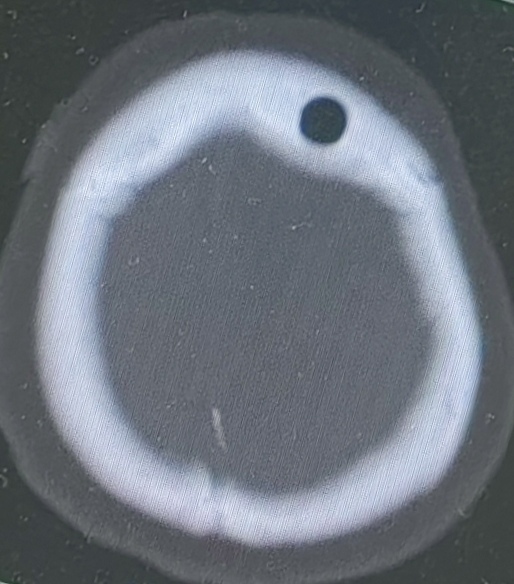

术后CT可见取材部位(气泡影)位于病变靶区(胼胝体前缘)